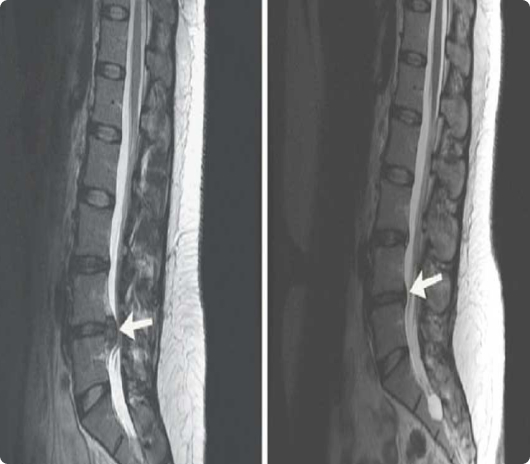

The patients we decided to observe had suffered from cLBP with or without radiculopathy symptoms in their legs for greater than 6 months. Prior to enrollment, all patients underwent physical therapy and at least 4 invasive treatments without relief. Failed treatments included BMC or PRP injections, intradiscal or intraarticular zygapophyseal joints, or combinations of both. Fluoroscopically guided epidural injections of corticosteroids or PRP were additional failed treatments, as were radiofrequency neurotomies in the medial branch. Candidacy for enrollment was based on meeting the aforementioned criteria and by having magnetic resonance image (MRI) screenings (1.5 T) and plain-film radiographs performed 6 months before treatment. In addition, those MRI screenings and radiographs had to rule out the following concomitant conditions: (i) carcinoma, (ii) fracture, (iii) instability, or (iv) severe vertebral canal or intervertebral foramen stenosis.

Annulogram

The annulogram is a pain free fluoroscopic X-Ray examination of your discs. We inject a small amount of X-Ray contrast into the outer rim of your intervertebral discs. This determines if your discs are leaking. We can identify very small subtle disc tears (even before they cause herniation or degeneration.) Anything missed by an MRI or CT will show up in the annulogram.